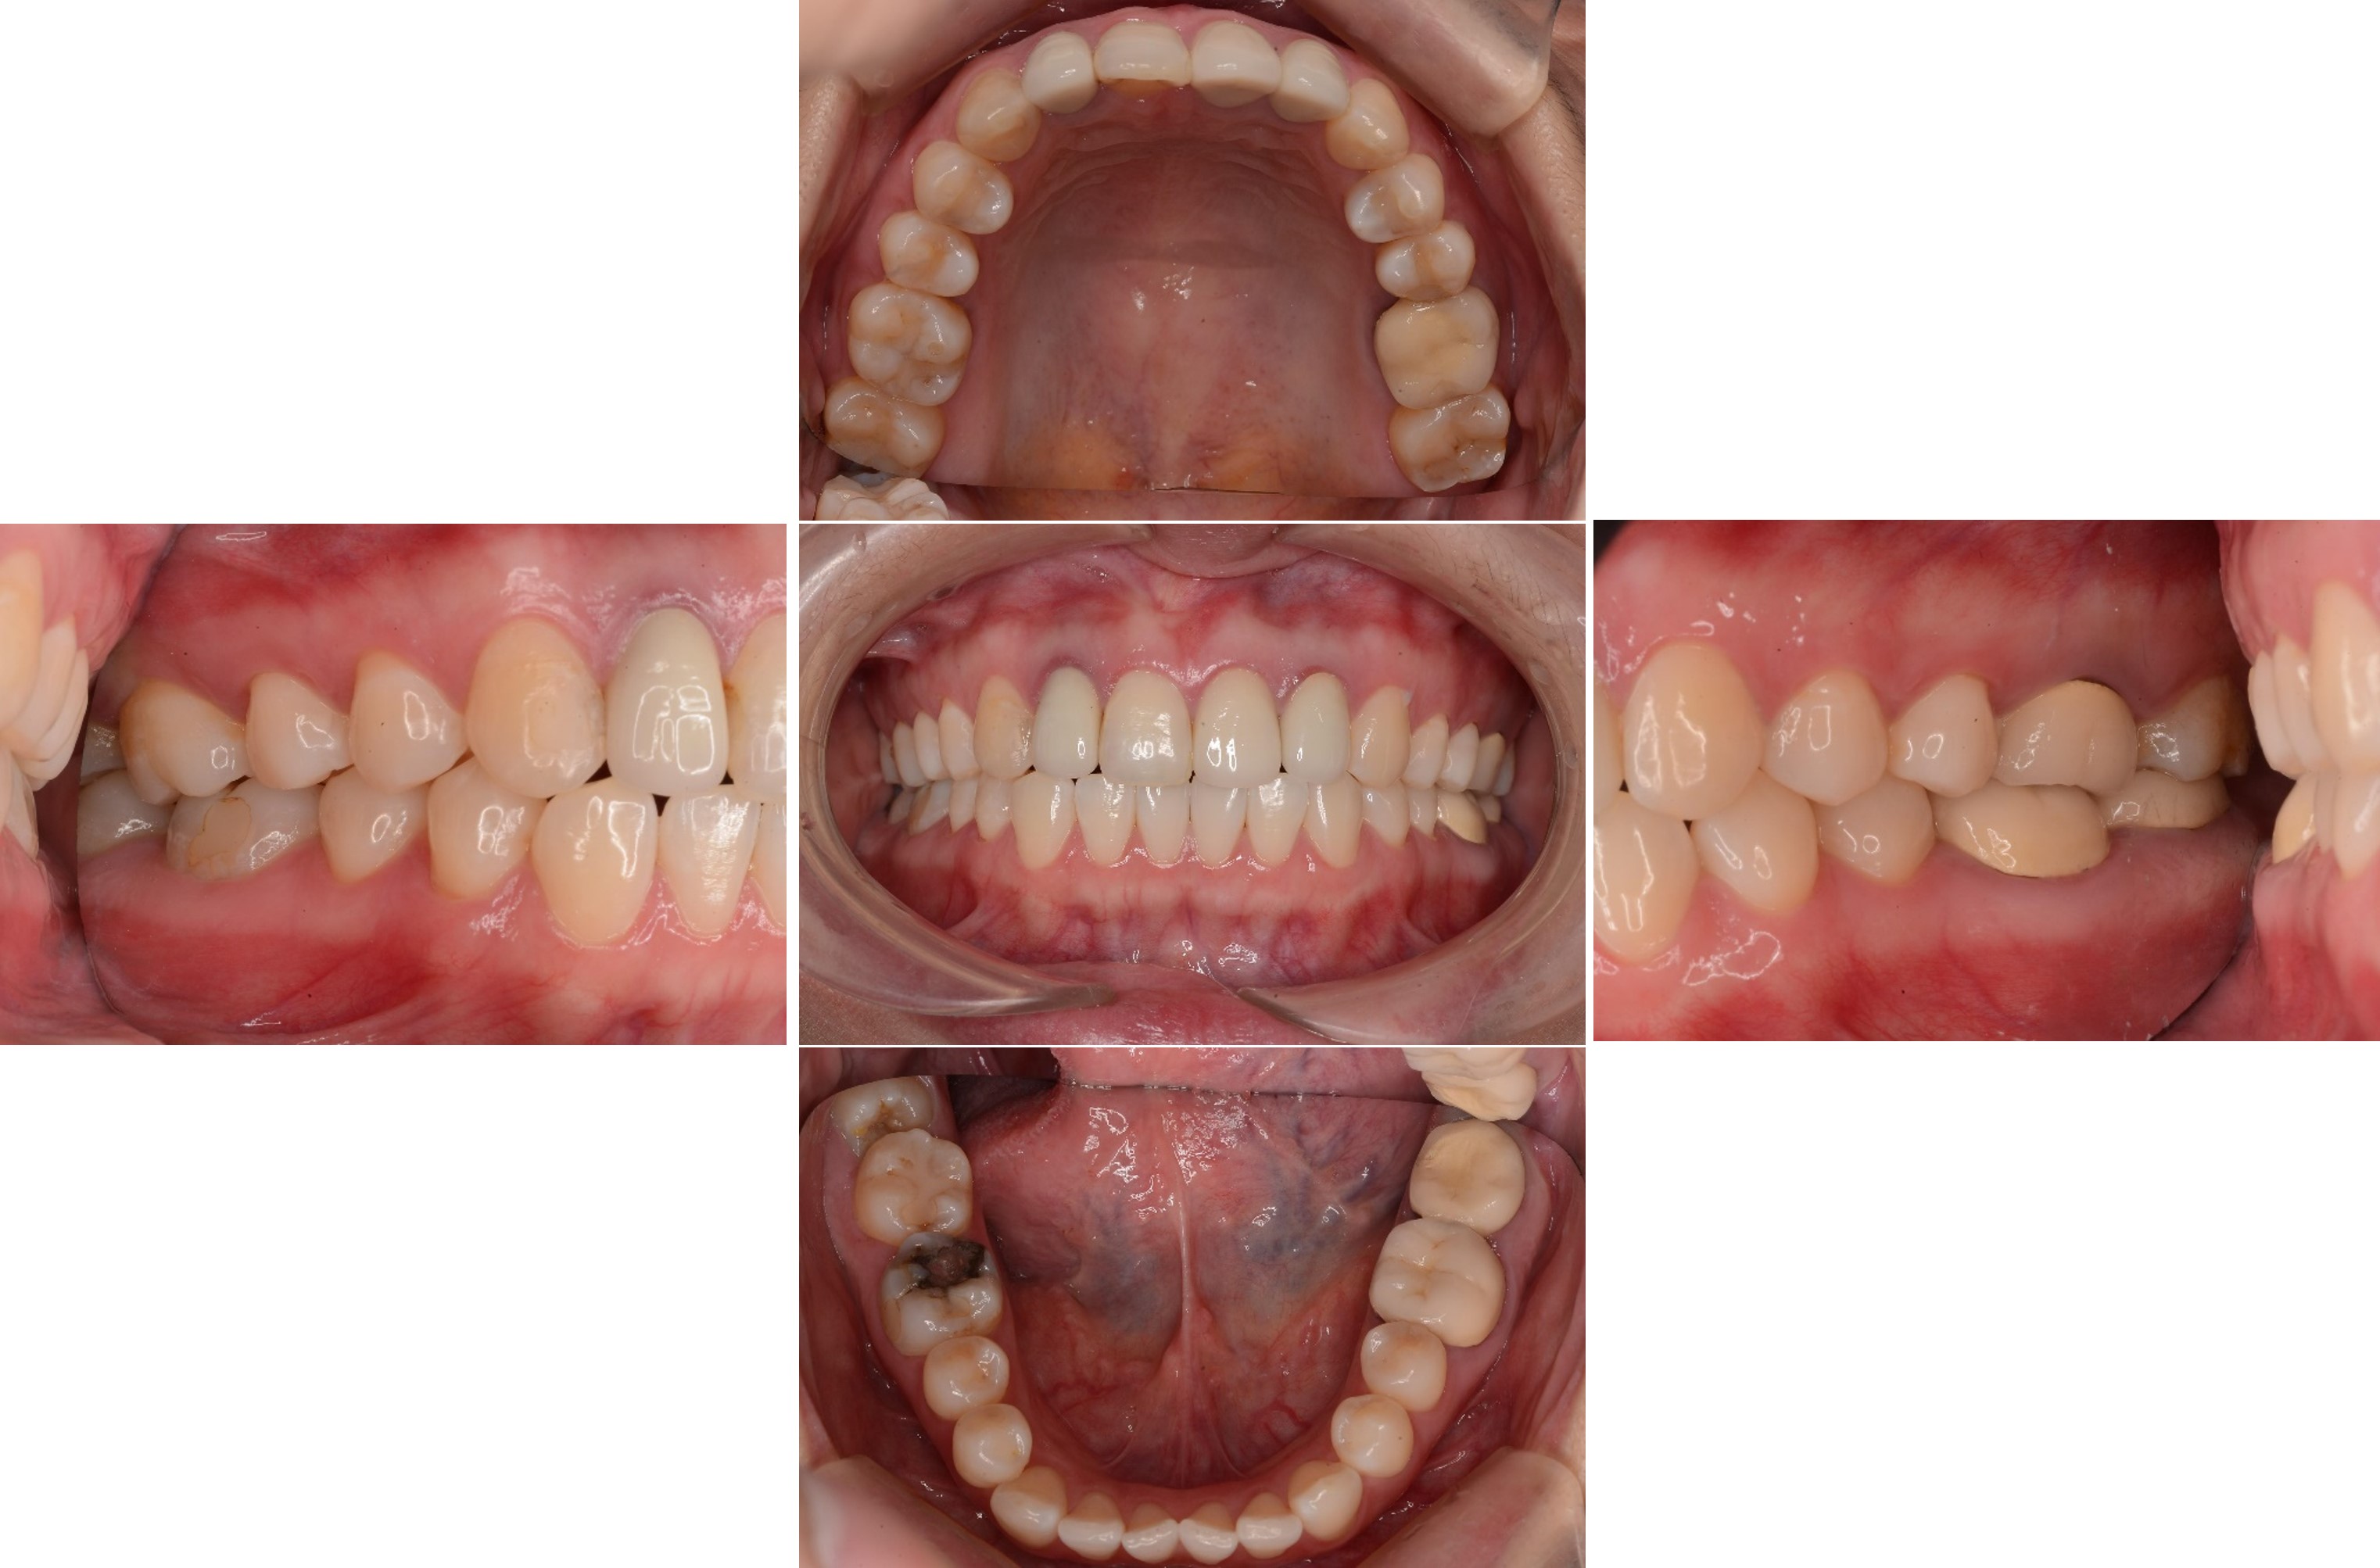

上顎前牙有瘻管,牙齒變色,右下有阻生齒與蛀牙

治療前,前牙病變,阻生齒等

治療前,牙齦旁有黑邊